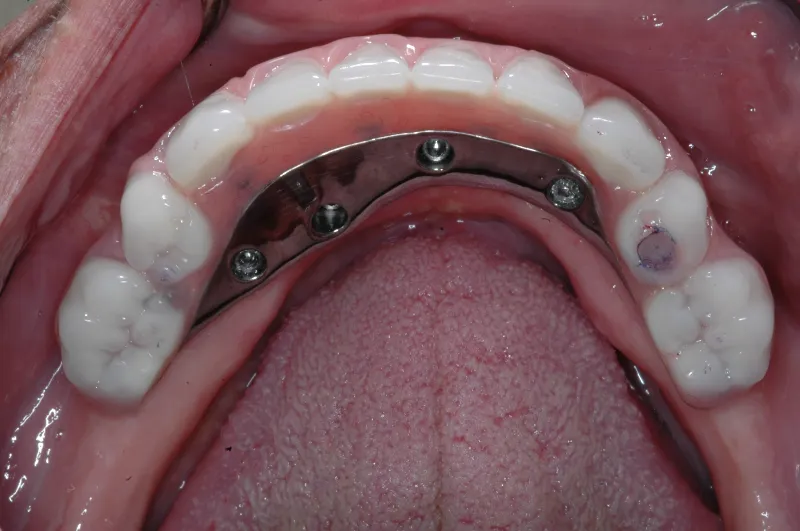

Implant dentures are designed to be fixed (screwed in place) or removable. The design is based on the number of implants present and the amount of bone loss that has already occurred. The fixed denture requires 4-6 implants . A removable implant supported denture can be made on as few as two implants. Sometimes the budget or insurance coverage will dictate which option you decide on. Most patients prefer the fixed type implant denture. These types of dentures eliminate the need for denture adhesive.